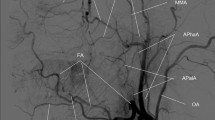

The main imaging parameters of the MR sequences were as follows. TOF: FOV 190 × 180 × 105 mm3, 6 slabs, voxel size 0.5 × 0.5 × 1 mm3, total acquisition time 6 min 37 s; SNAP: FOV 180 × 180 × 70 mm3, voxel size 0.8 mm isotropic, total acquisition time 3 min 45 s; ASL: using pseudo-continuous labeling scheme, FOV 240 × 240 × 125 mm3, voxel size 3 × 3 × 5 mm3, labeling duration 1800 ms, post labeling delay 2000 ms, total acquisition time 4 min 55 secs; PC: FOV 180 × 180 × 70 mm3, voxel size 0.5 × 0.5 × 1 mm3, encoding velocity 100 cm/s in all three directions, total acquisition time 5 min 4 s; iSNAP: FOV 204.8 × 179.2 × 144 mm3, voxel size 0.8 mm isotropic; 2D T2W FLAIR: FOV 230 × 230 mm2, in-plane resolution 1.28 × 1.28 mm2, slice thickness 4 mm, gap between slices 1 mm, 25 slices, total acquisition time 2 min. Note that the FOVs of the SNAP and 3D PC scans were purposely positioned upwards to cover more distal arteries, with the distance between circle of Willis and inferior edge of FOV being around 13 mm (Fig. 1)17. Other details of the protocols of TOF, SNAP, ASL and PC were described elsewhere17.

Processing of TOF, SNAP, ASL and PC has also been detailed previously17. In brief, by using a custom-designed dedicated analysis tool named iCafe20, the intracranial arteries on TOF or SNAP images were semi-automatically traced to generate centerlines, which were subsequently manually labeled by a trained reviewer (Fig. 2a,b). Then the total length, number of branches, and average branch-wise tortuosity of the anterior cerebral arteries distal to A1, middle cerebral arteries distal to M1 and posterior cerebral arteries distal to P1 were calculated. To obtain the total arterial length, length of each arterial segment was first calculated by summing up the Euclidean distances between the centerline points and then added together over all segments. Number of branches is the number of arterial segments which start from a bifurcation and end in another bifurcation or termination in a vascular group. To achieve a fair comparison, the TOF images were cropped to obtain the same coverage as SNAP before calculating the vascular features17. The quantification of the above-mentioned intracranial vascular features using iCafe has been previously reported as highly reproducible14. iSNAP T1W images were used to perform brain segmentation (Fig. 2c) using SPM12 (https://www.fil.ion.ucl.ac.uk/spm). CBF maps (Fig. 2d) and mean gray matter CBF (in ml/100 g/min) were calculated from ASL images8. Cross sectional PC images were generated near the middle of internal carotid arteries and the basilar artery, and artery contours were drawn semi-automatically (Fig. 2e). Then, whole-brain mean PC CBF (in ml/100 g/min) was calculated as the total volume flow rate (i.e. mean velocity multiplied by area) of the two internal carotid arteries and the basilar artery, divided by the product of total brain volume (i.e. total volume of gray matter and white matter obtained from the brain segmentation) and brain density (assumed to be 1.06 g/ml)16.

Illustration of image analyses. (a,b): TOF (a) and SNAP (b) MRA images (upper panels), and the corresponding traced and labeled intracranial arteries (bottom panels). (c): A representative slice of the T1-weighted image (upper left panel), binary brain mask (upper right panel) and gray matter mask (bottom right panel). (d): A representative slice of the ASL perfusion weighted image (upper panel) and the corresponding CBF map (bottom panel). (e): The MRA image (upper panel) obtained from PC complex difference image, and the cross-sectional PC complex difference images and PC velocity images of the RICA, LICA and basilar artery (bottom panel). The arterial contours were depicted on the PC complex difference image and then mapped to PC velocity image. (f): A representative slice of FLAIR image (upper panel) and the segmented white matter hyperintensity (red region).